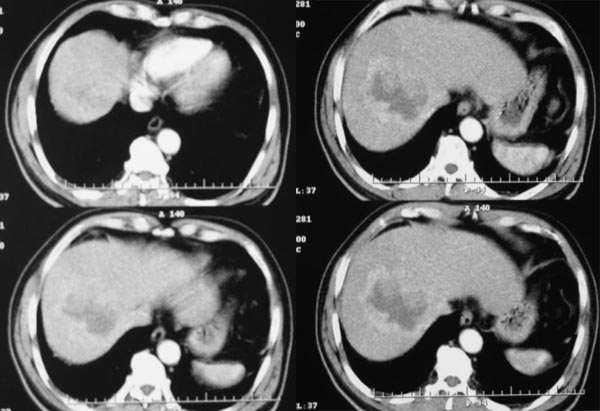

动脉期

2.病灶特点:平扫呈低密度,密度不均,中央呈更低密度;动脉期病灶周围强化较明显,高于正常肝组织,低于同层主动脉密度,中央坏死区未见明显强化;门静脉期,病灶呈低密度,低于正常肝组织密度。

肿瘤实质的强化特点符合肝癌表现,需要注意的地方还有患者可能存在门脉右支和下腔静脉内癌栓形成,这更加支持肝癌的诊断。

肿瘤的生长特点和强化特点符合纤维板层样肝细胞癌,下腔静脉内在动脉期有充盈缺损,而在静脉期内未见充盈缺损,故不考虑下腔静脉瘤栓形成

2、动脉期:病灶边缘强化明显,明显高于肝实质,中间未强化为坏死区

3、门脉期:病灶呈低密度,低于肝实质,下腔静脉见充盈缺损,说明癌栓形成